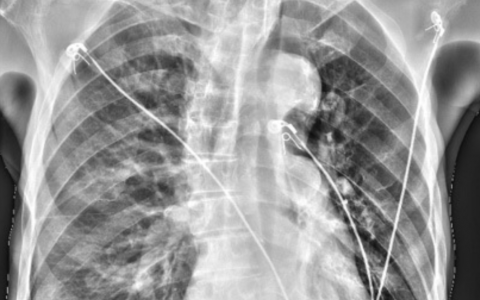

A 62-year-old man presented to the hospital with a 1-month history of muscle aches and weakness in the anterior thighs and the lower posterior aspect of both legs and weight loss of 10 kg. On physical examination, there was numbness of the anterior thighs and posterior lower legs but no skin changes or abdominal tenderness. Laboratory tests showed elevated levels of inflammatory markers. Findings on computed tomography of the chest, abdomen, and pelvis were unremarkable. Tests for antineutrophil cytoplasmic antibodies were negative. Abdominal angiography was performed, shown in the left and right images. What other condition is associated with this patient’s diagnosis?

一名62岁男性因前大腿和双腿下部后侧肌肉疼痛和无力,以及体重下降10公斤,持续1个月而前往医院。体格检查发现前大腿和后小腿麻木,但没有皮肤变化或腹部压痛。实验室检测显示炎症标志物水平升高。胸部、腹部和盆腔的计算机断层扫描结果无异常。抗中性粒细胞胞浆抗体检测为阴性。进行了腹部血管造影,左侧和右侧图像显示。与这位患者的诊断相关的其他疾病是什么?